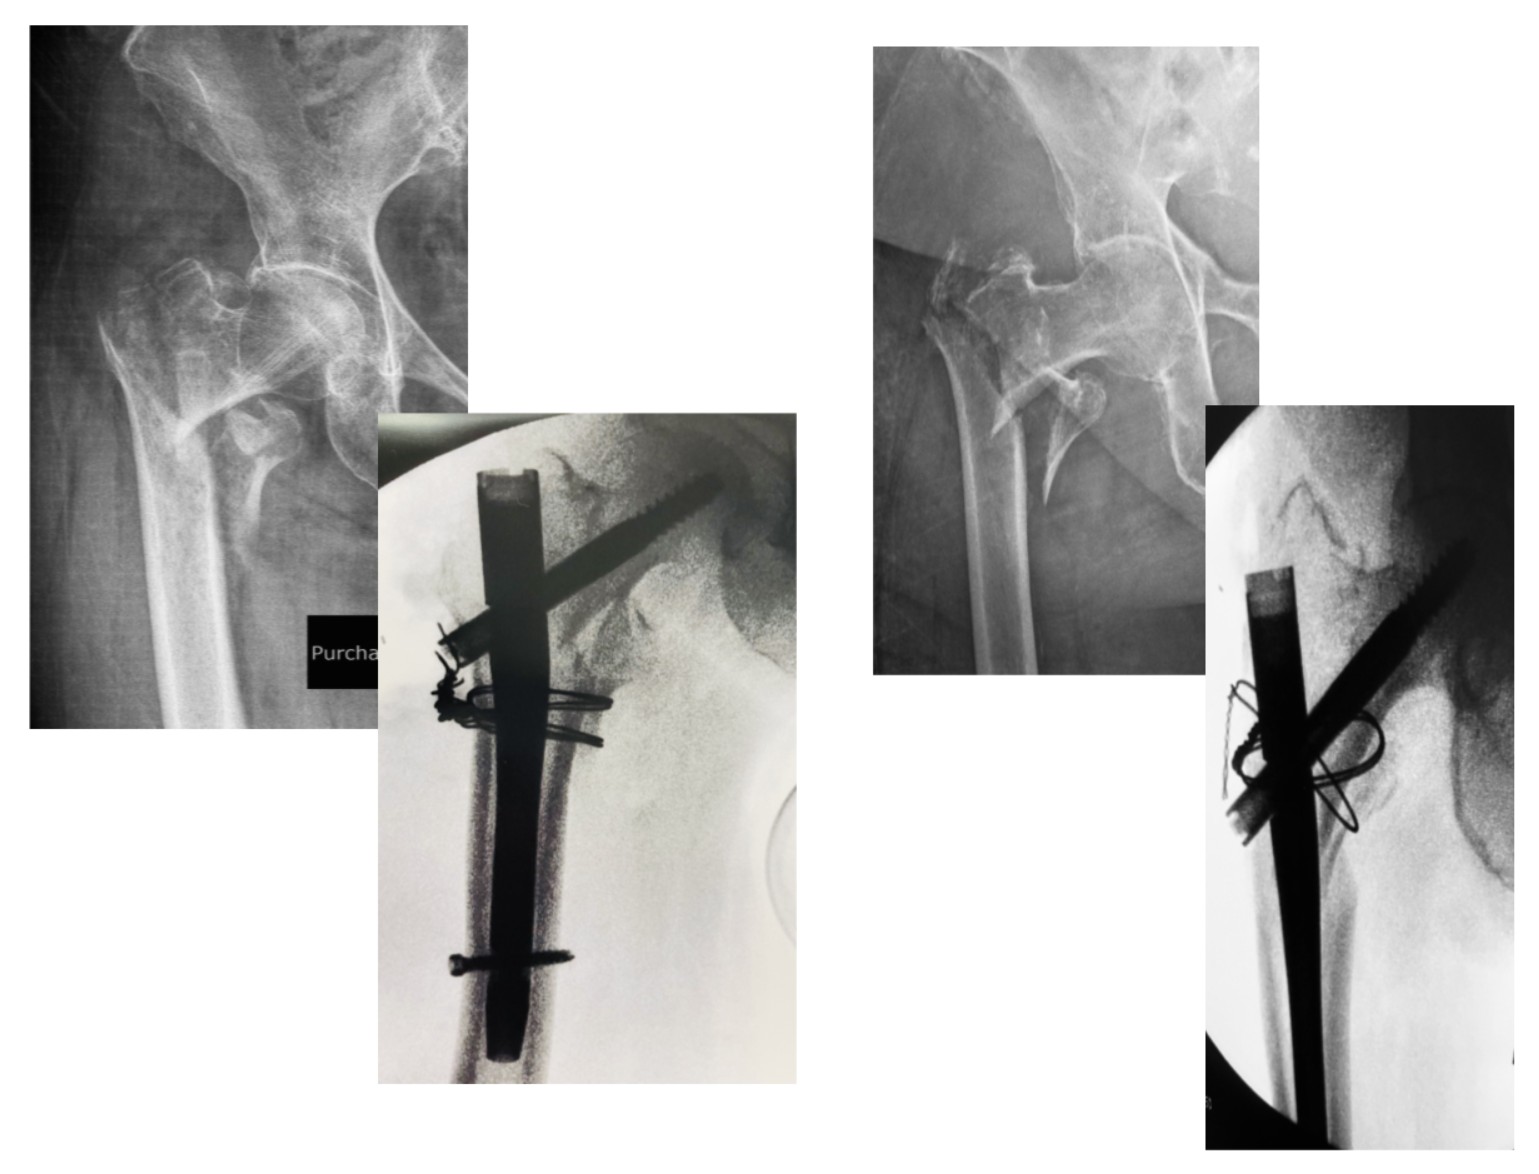

Στις εικόνα 11 και εικόνα 12 ημιαρθροπλαστική AMIS για υποκεφαλικό κάταγμα ισχίου, από προσωπικό αρχείο